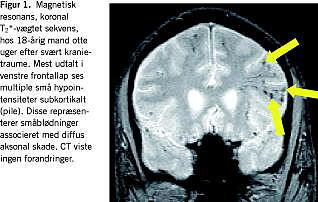

Såkaldte T2 *-vægtede sekvenser har høj sensitivitet for hæmoglobinderivater og er derfor specielt egnede til detektion af blødninger. Petekkiale blødninger ledsagende DAI bliver herved synlige [3] (Figur 1 ). Alligevel tillader T2 *-vægtning kun visualisering af et mindretal af DAI-læsioner, idet man fra autopsistudier ved at mere end 80% af DAI-læsioner er nonhæmoragiske. Antallet af synlige DAI-læsioner på T2 *-vægtede billeder er da heller ikke nogen god prognostisk markør. Punktformede hypointensiteter ved prædilektionssteder for DAI, dvs. subkortikal hvid substans, corpus callosum og dorsolaterale mesencefalon er ikke desto mindre indikativt for tilstedeværelse af en svær primær diffus hjerneskade.